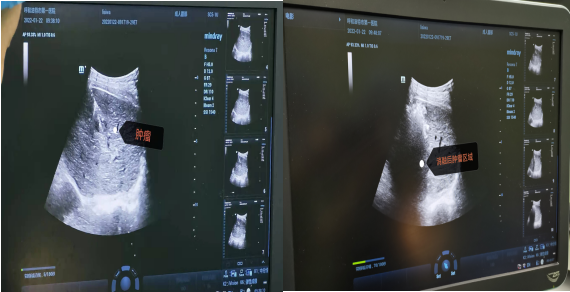

病例2. 患者,男,63岁,因上腹部憋胀不适1月余入院,患者入院前已经辗转区内多家医院诊治。术前评估检查全腹增强CT:肝硬化,脾切除术后,肝S6段小肝癌,肿瘤直径约2cm;甲胎蛋白15.05ng/ml。肿瘤位于肝脏右后叶,位置深,腹腔镜手术操作因合并基础疾病及手术史,恐无法受益。因选择消融治疗具有对肝功能影响少,创伤小,疗效确切的特点。经团队讨论后决定行消融治疗,于2022年1月22日在外院专家指导下,全麻超声引导行肝肿瘤射频消融术。消融治疗主要适用于CNLC Ia期及部分Ib期肝癌(即单个肿瘤、直径≤5cm,或2-3个肿瘤最大直径≤3cm无血管、胆管和邻近器官侵犯及远处转移,可获得根治性治疗效果)。术后患者肝功能恢复正常,无并发症痊愈出院。